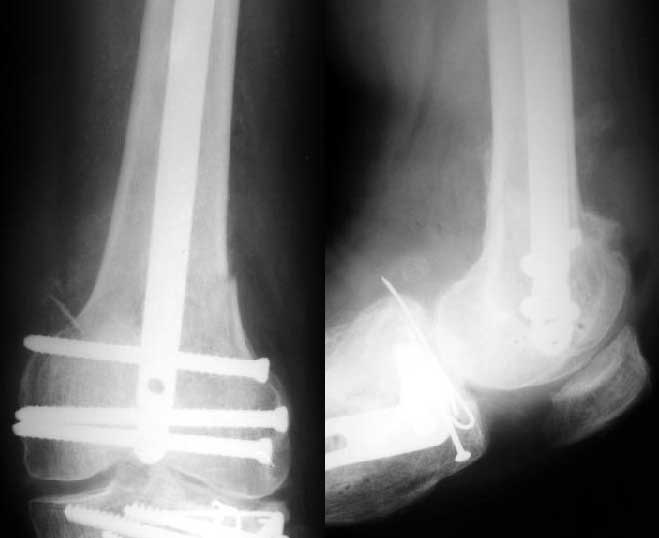

1

2

I attached an example of C2 fracture with result of the same technique in 5 months.